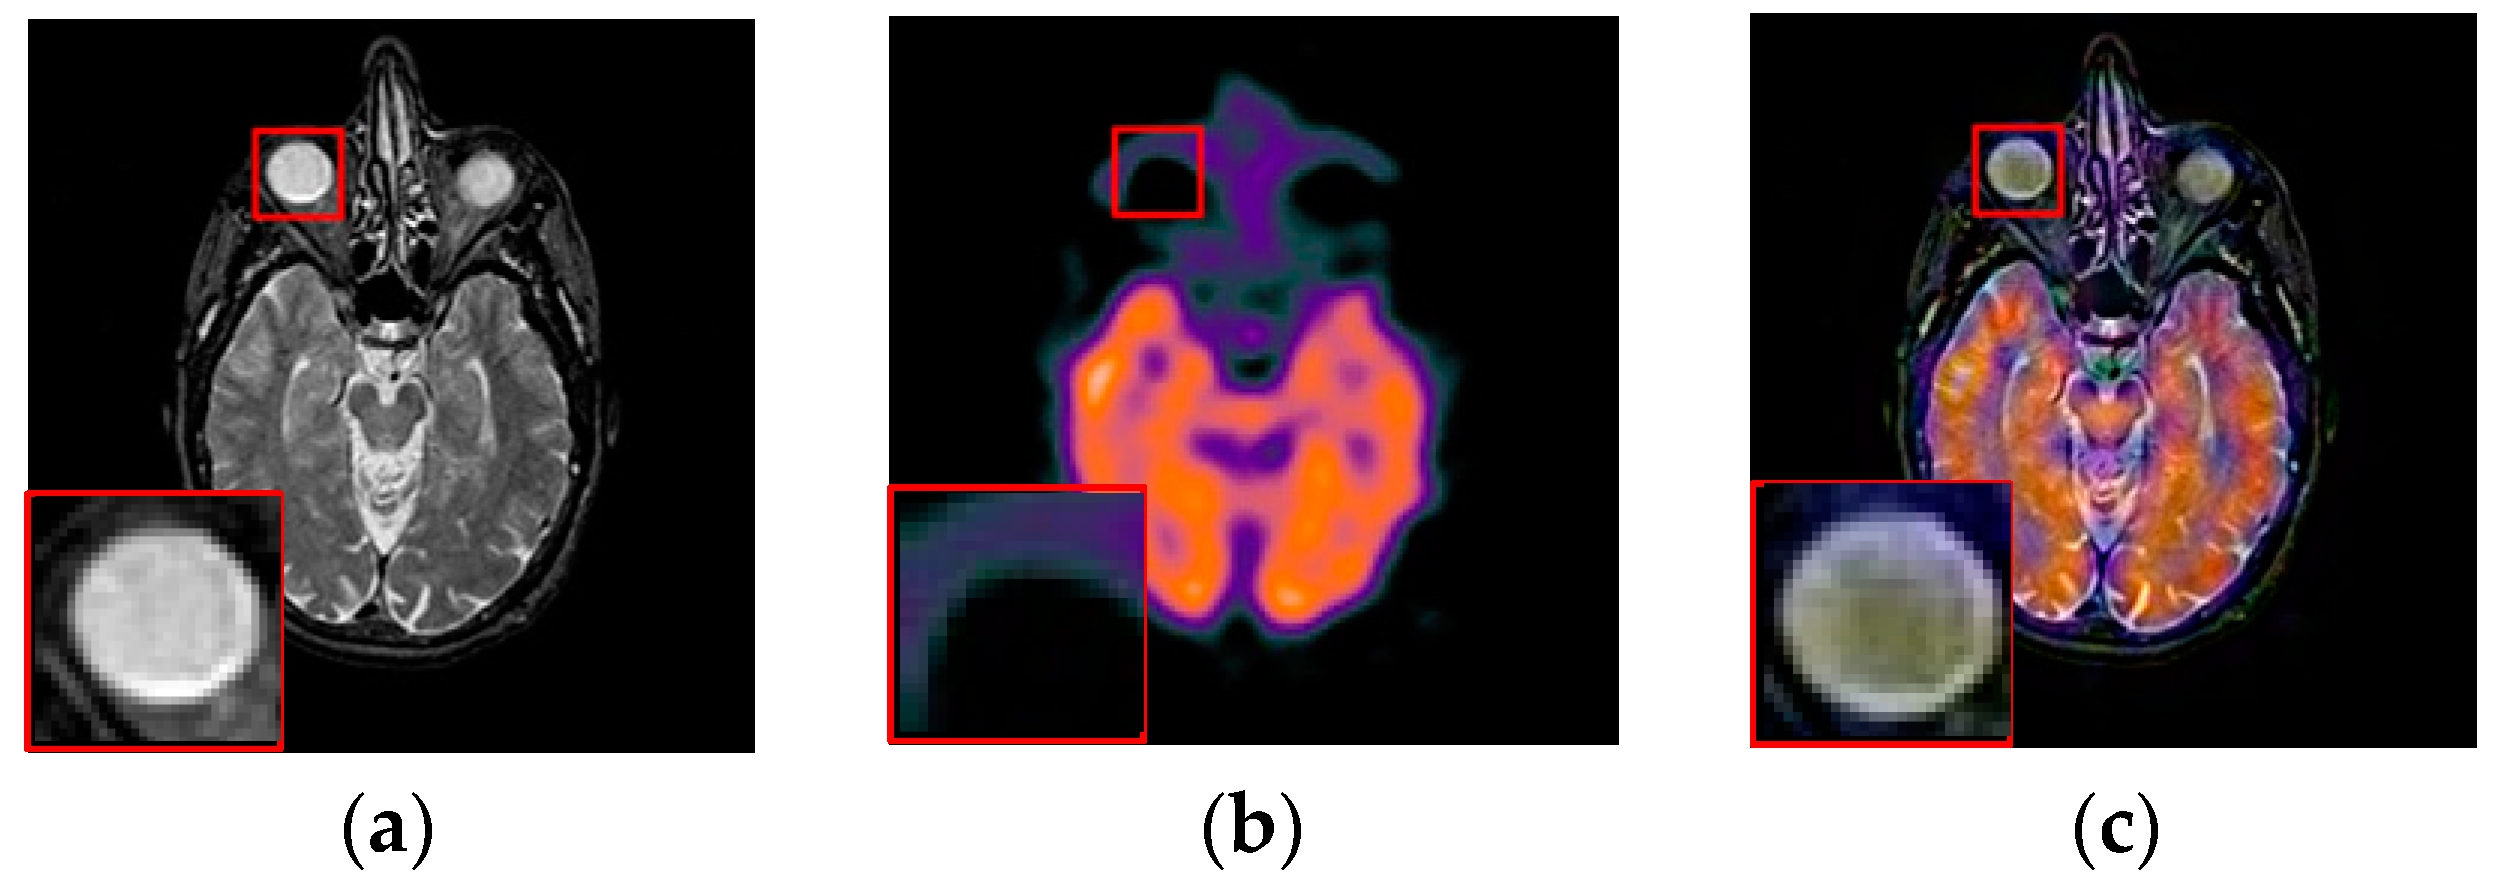

To further demonstrate that the proposed method is equally effective for other types of medical image fusion, we test the other two categories of medical image fusion systems include MRI/SPECT and MRI/PET, and the fusion results are shown in Figure 9 and Figure 10. The details of fused images are zoomed in and presented in the bottom left corners of their respective images.

Figure 9.

Fused results of MRI/SPECT medical images by different methods. (a) MRI; (b) SPECT; (c) DCTWT; (d) Curvelet; (e) NSCT; (f) Liu-ASR; (g) Kim; (h) Zhu; (i) Proposed.

Figure 10.

Fused results of MRI/PET medical images by different methods. (a) MRI; (b) PET; (c) DCTWT; (d) Curvelet; (e) NSCT; (f) Liu-ASR; (g) Kim; (h) Zhu; (i) Proposed.

With more careful observation, we can see that the spatial edge details and brightness information in Figure 9i and Figure 10i are more accurate compared with Figure 9c–h and Figure 10c–h generated by the six compared methods. This means the useful information from source images have been successfully transformed into the fused images, that is, our fused results have the best visual features. This is mainly because the novel construction of the overcomplete dictionary in this paper is composed of two parts include the brightness sub-dictionary and the edge detail sub-dictionary, which can fully express the significant features of the medical images. This will be very beneficial to the implementation of medical image fusion in practical medical assistance applications. In conclusion, the proposed algorithm has the best subjective visual effect.

3.6. Extension to Other Type Image Fusion Issues

To exhibit the generalization ability of the proposed method, we extend its application to other types of image fusion including multifocus image fusion, panchromatic-multispectral image fusion and infrared-visible image fusion. The three fusion examples are shown in Figure 11, where the source images are displayed in the first two columns, and the fused results are listed in the last column. We can notice that the important feature include detail, sharp, edge and brightness feature et al. of source images are well preserved in the fused image. Among them, the fusion performance of infrared-visible image fusion is relatively high. This demonstrates that the proposed model can transfer useful information from the source images into the fused result [49]. Meanwhile, fewer undesirable artifacts are introduced in these fusion process, which indicate our method has strong robustness in these applications. Furthermore, compared with MRI and PET imaging, some new functional medical imaging modality, such as photoacoustic computed tomography (PACT) [50], resting-state functional connectivity (RSFC) and functional connectivity photoacoustic tomography (fcPAT) [51] etc., can offer better spatial resolutions with a fast, noninvasive and non-ionizing imaging modality to describe the brain physiology and pathology. Therefore, further study will be required to investigate them for image fusion in the near future.

Figure 11.

Other types of image fusion examples using the proposed method.